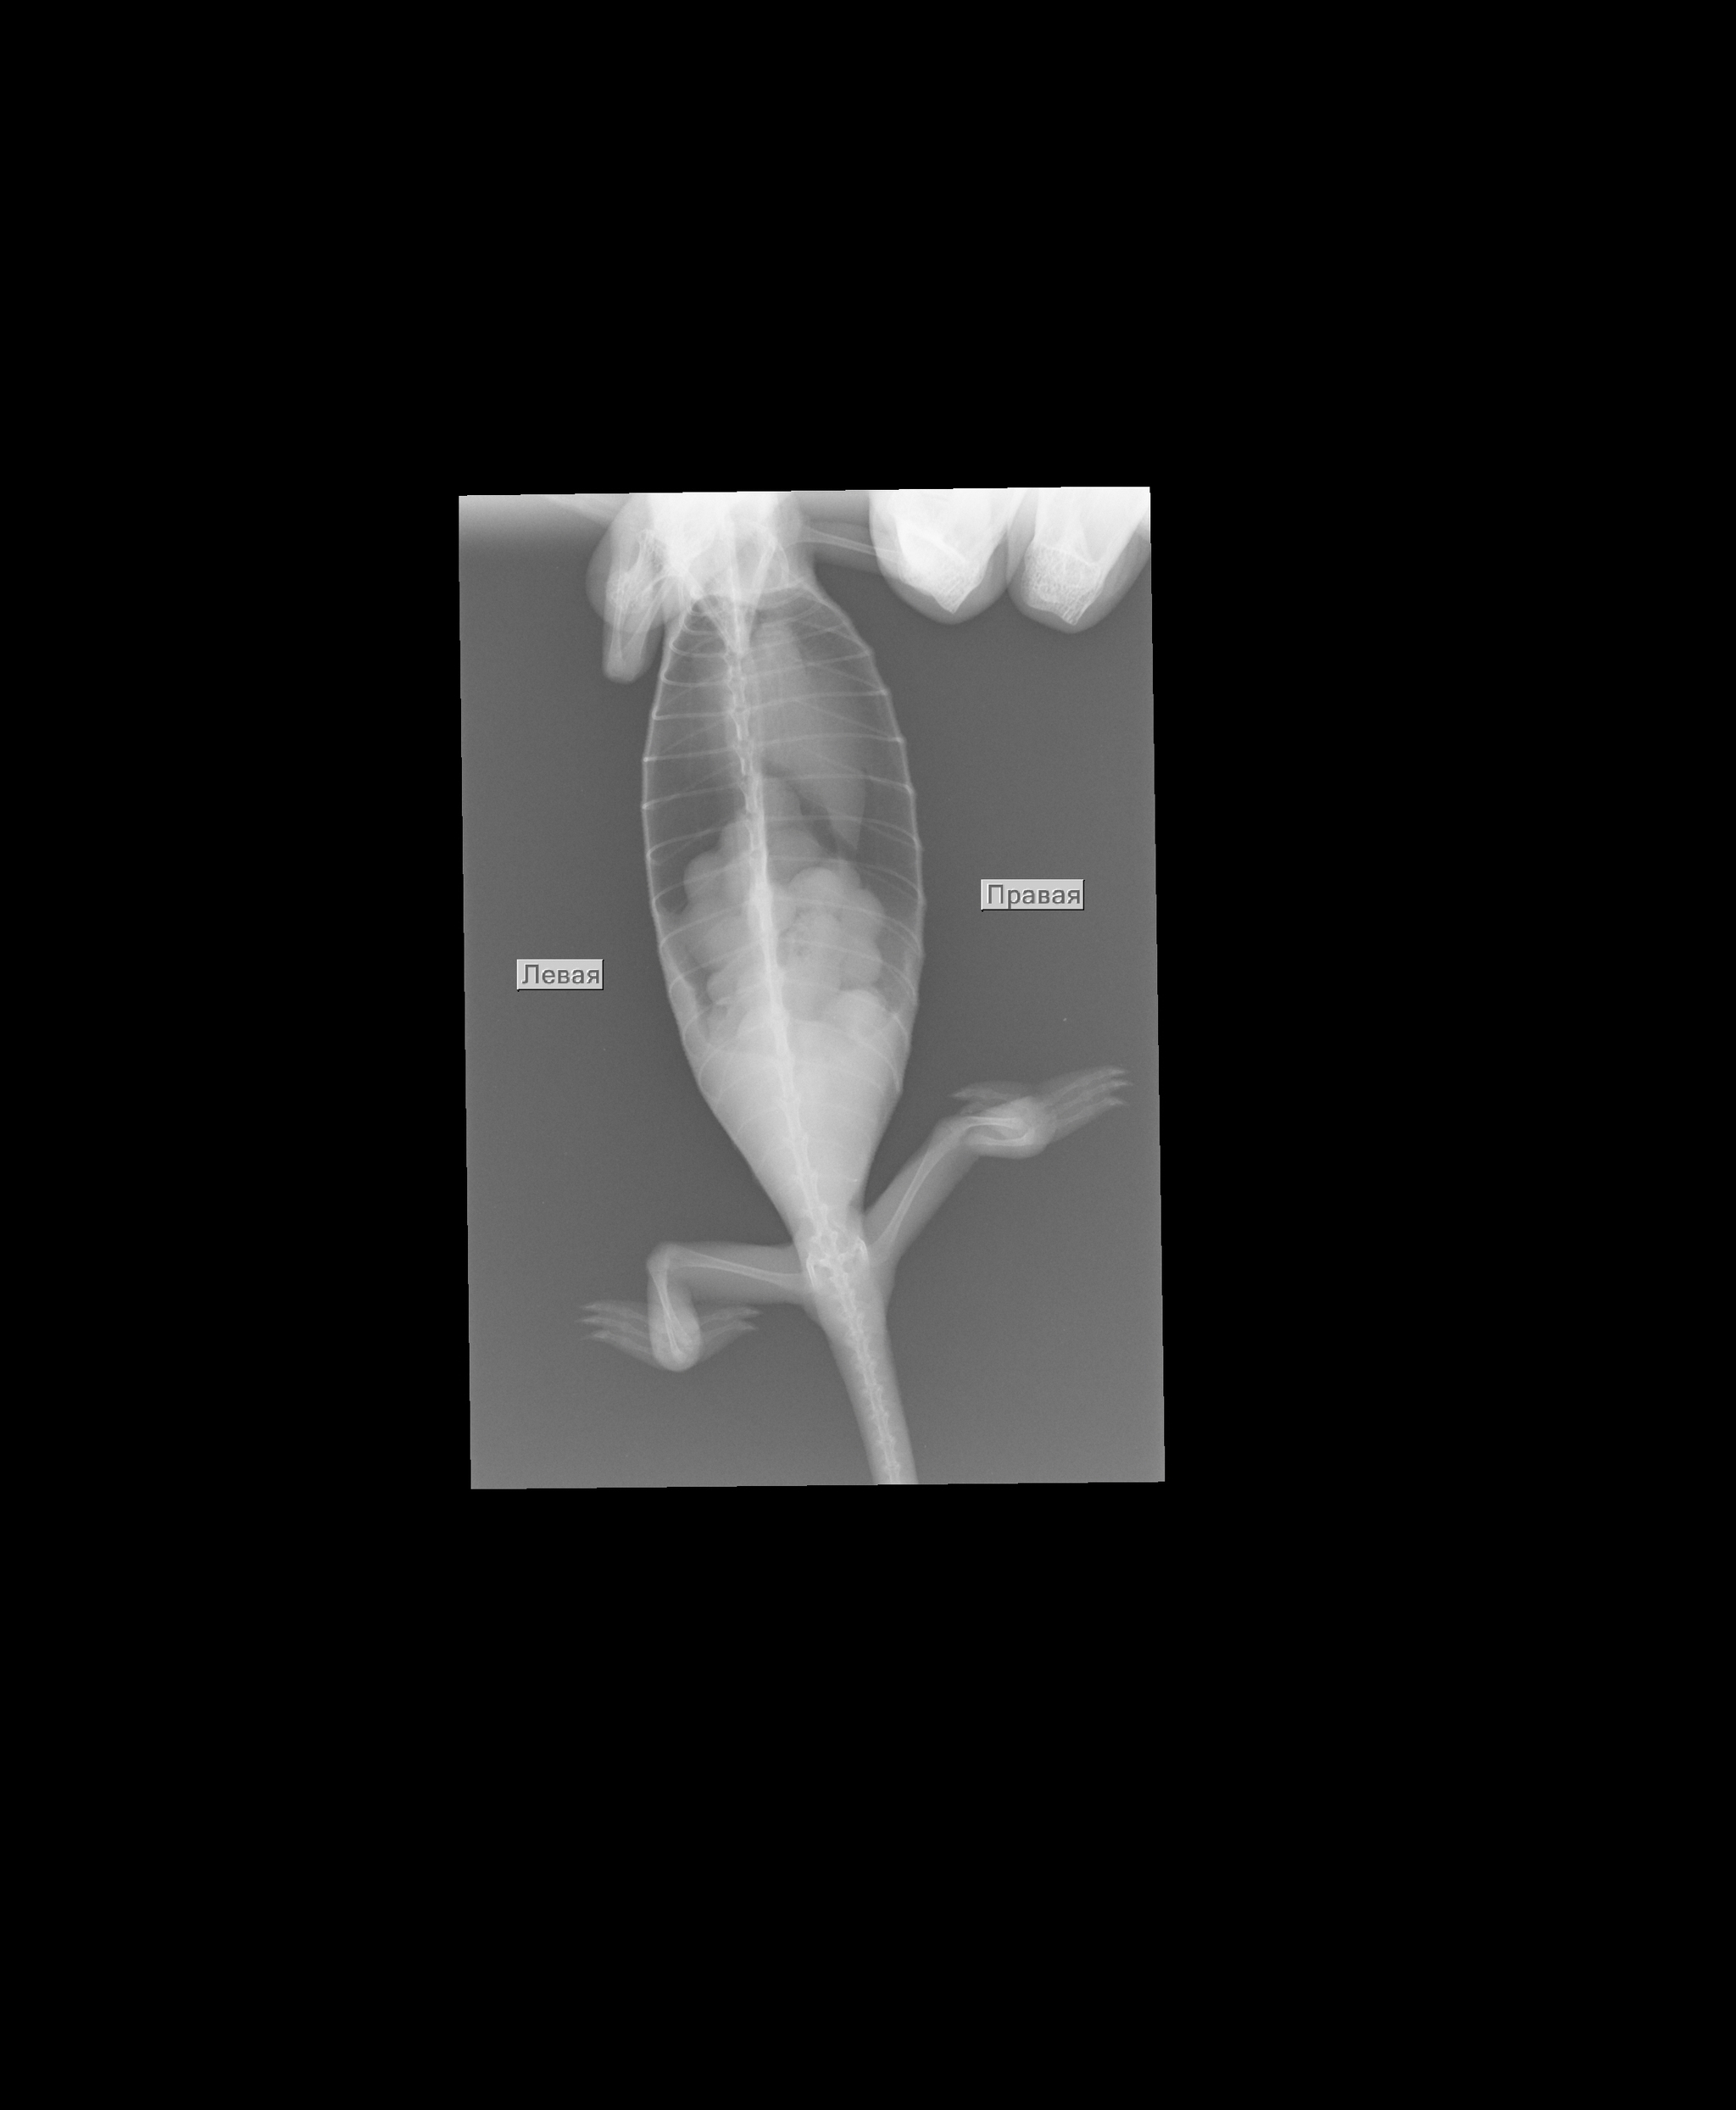

Было назначено: сдача стула на паразитов, рентген плюс анализ крови, чтобы хоть как-то попытаться определить причину болезни.

Проблем с паразитами не было, а вот на рентгене был какой то не переваренный кусок еды. Это могло быть что-то из декора, что он по глупости съел и теперь не может из себя вывести. Тогда пришлось бы делать операцию.

Анализ крови показал, что у Хамона больная печень и не хватает кальция.